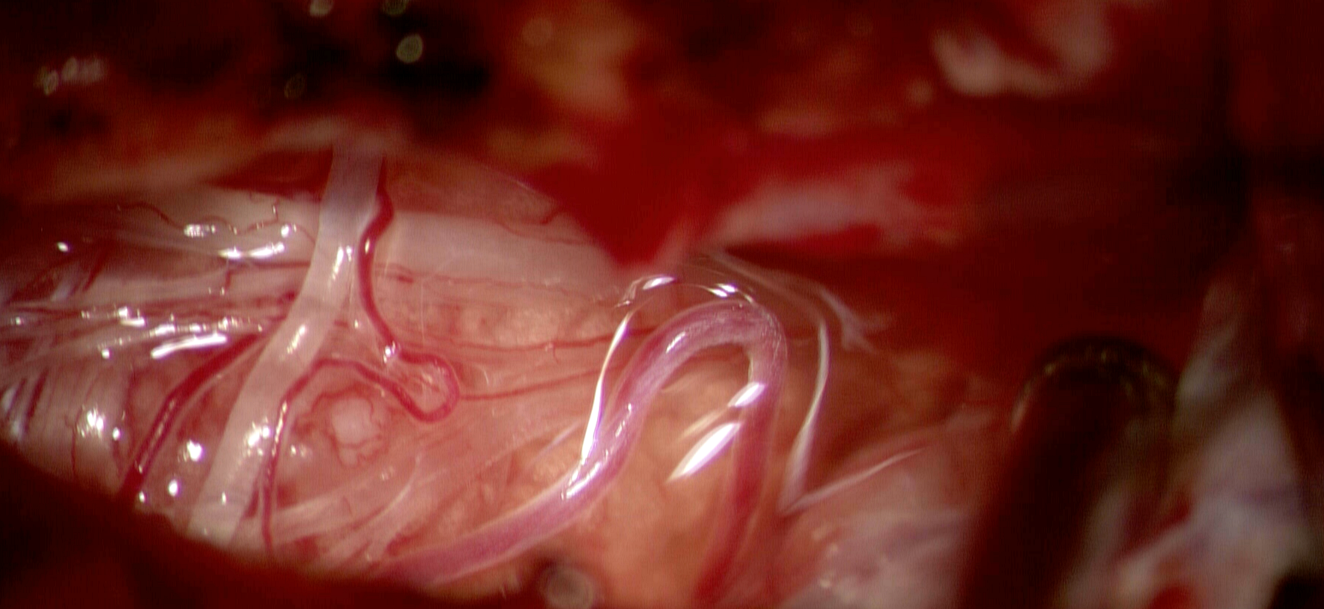

După deschiderea durei, tumora a fost identificată ca o formațiune bine delimitată, aderentă la dura mater pe partea stângă.

Disecția s-a realizat sub microscop operator, cu separarea progresivă a tumorii de măduva comprimată.

În aceste momente, chirurgia devine un exercițiu de finețe:

nu este vorba doar de a îndepărta tumora, ci de a proteja fiecare fibră funcțională.

Pe măsură ce tumora a fost excizată, măduva și-a recăpătat treptat forma și poziția.

Semnalele de neuromonitorizare au rămas stabile pe tot parcursul intervenției, confirmând protejarea funcției neurologice.